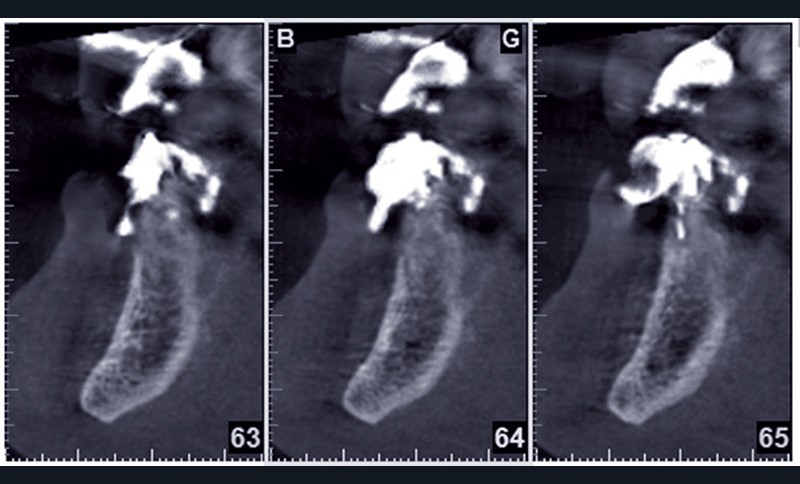

Cette ostéointégration est confirmée par le Cone Beam(fig. 4a et b).